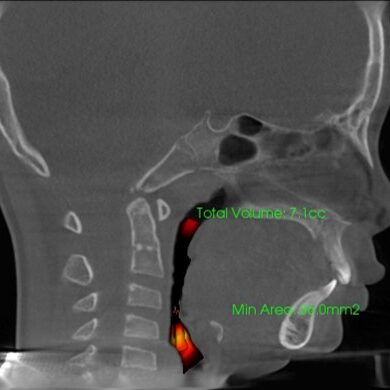

気道容積:治療前7.1 cc

気道容積:治療中11.3cc